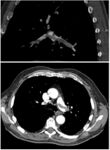

Large saddle embolus seen in the pulmonary artery (white arrows).

CT pulmonary angiography showing a "saddle embolus" at the bifurcation of the main pulmonary artery and thrombus burden in the lobar arteries on both sides.